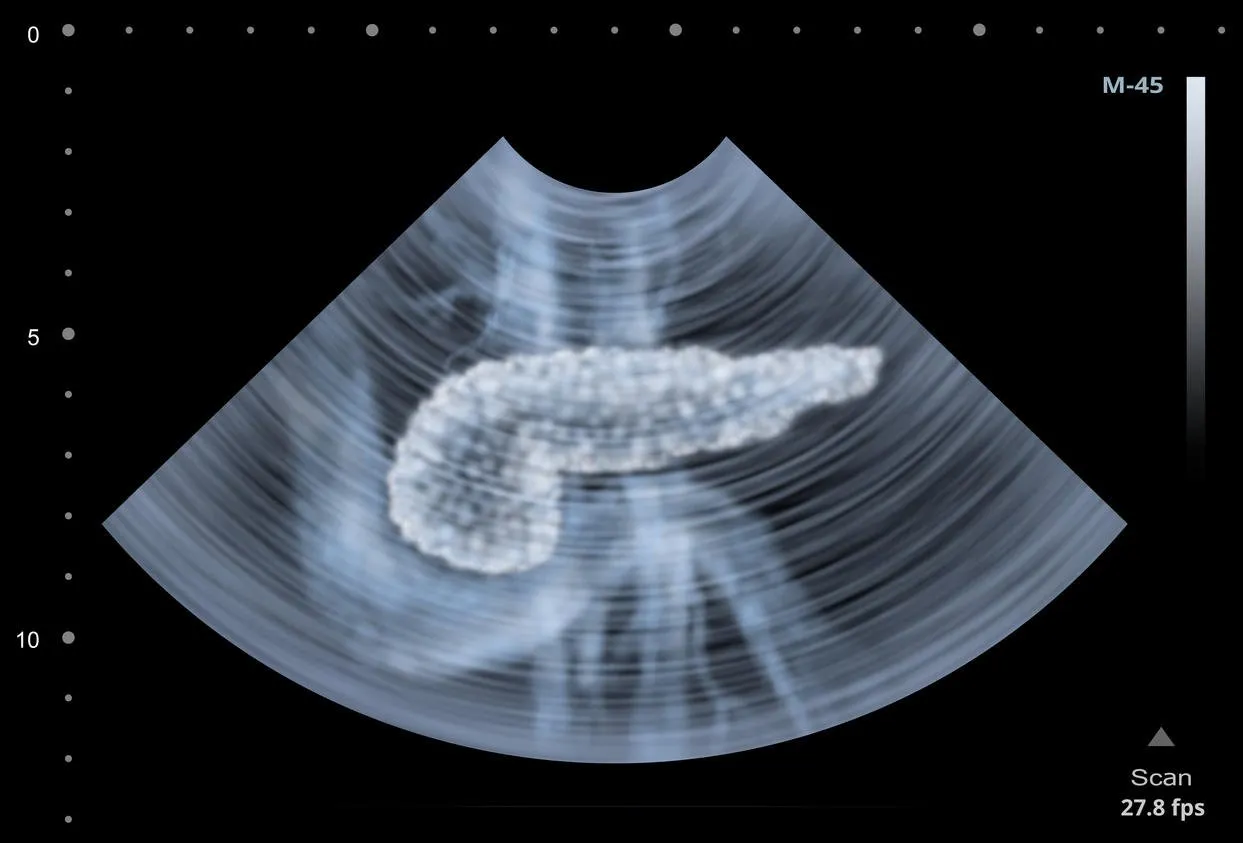

ultrasound scan of human pancreas illustration

La deuxième grande fonction du pancréas est dite endocrine, c’est-à-dire qu’il joue un rôle dans "la régulation du taux de sucre dans le sang (la glycémie) par la sécrétion d’insuline notamment", ajoute le Pr Crenn. C’est pourquoi "une augmentation de la glycémie" peut également être un signe révélant un dysfonctionnement du pancréas. "Ce signe peut d’ailleurs lui-même être asymptomatique ou découvert sur un symptôme complètement autre que pancréatique", précise-t-il.